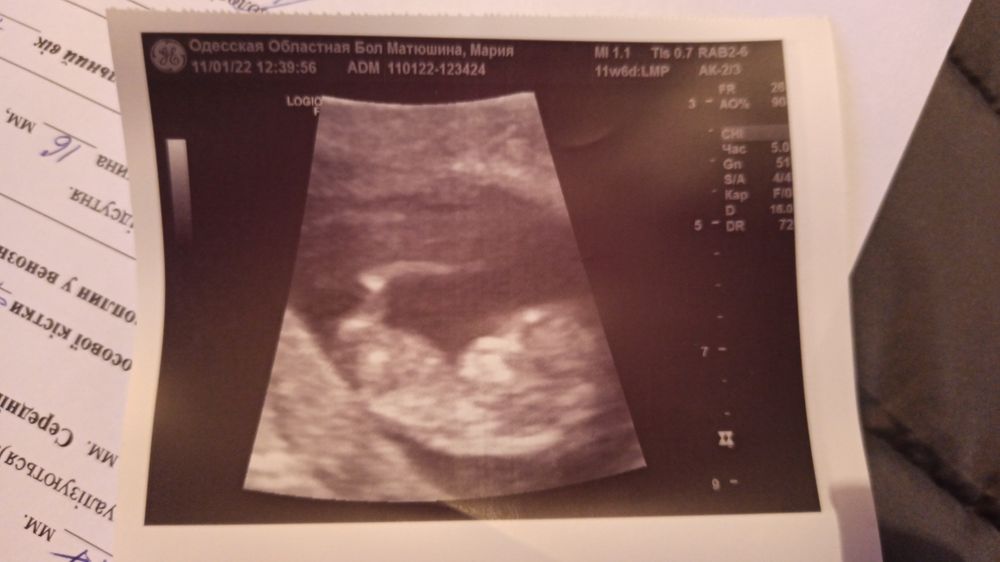

Назначили скрининг на 13января, а сделала 11 го у другого врача. Хотела просто глянуть, как там малыш, так как анализы сначала, а потом УЗИ. А он взял и отскринил. Приложил датчик, а там танцепляски 47 миллиметрового человечка😍😍😍 🙏 Благодарю Всевышнего, а то накрутила себя.

На скрининге уже все хорошо, ни тонуса, ни гематомы. И человек с 12 мм вырос 47 мм. Сердце 160.